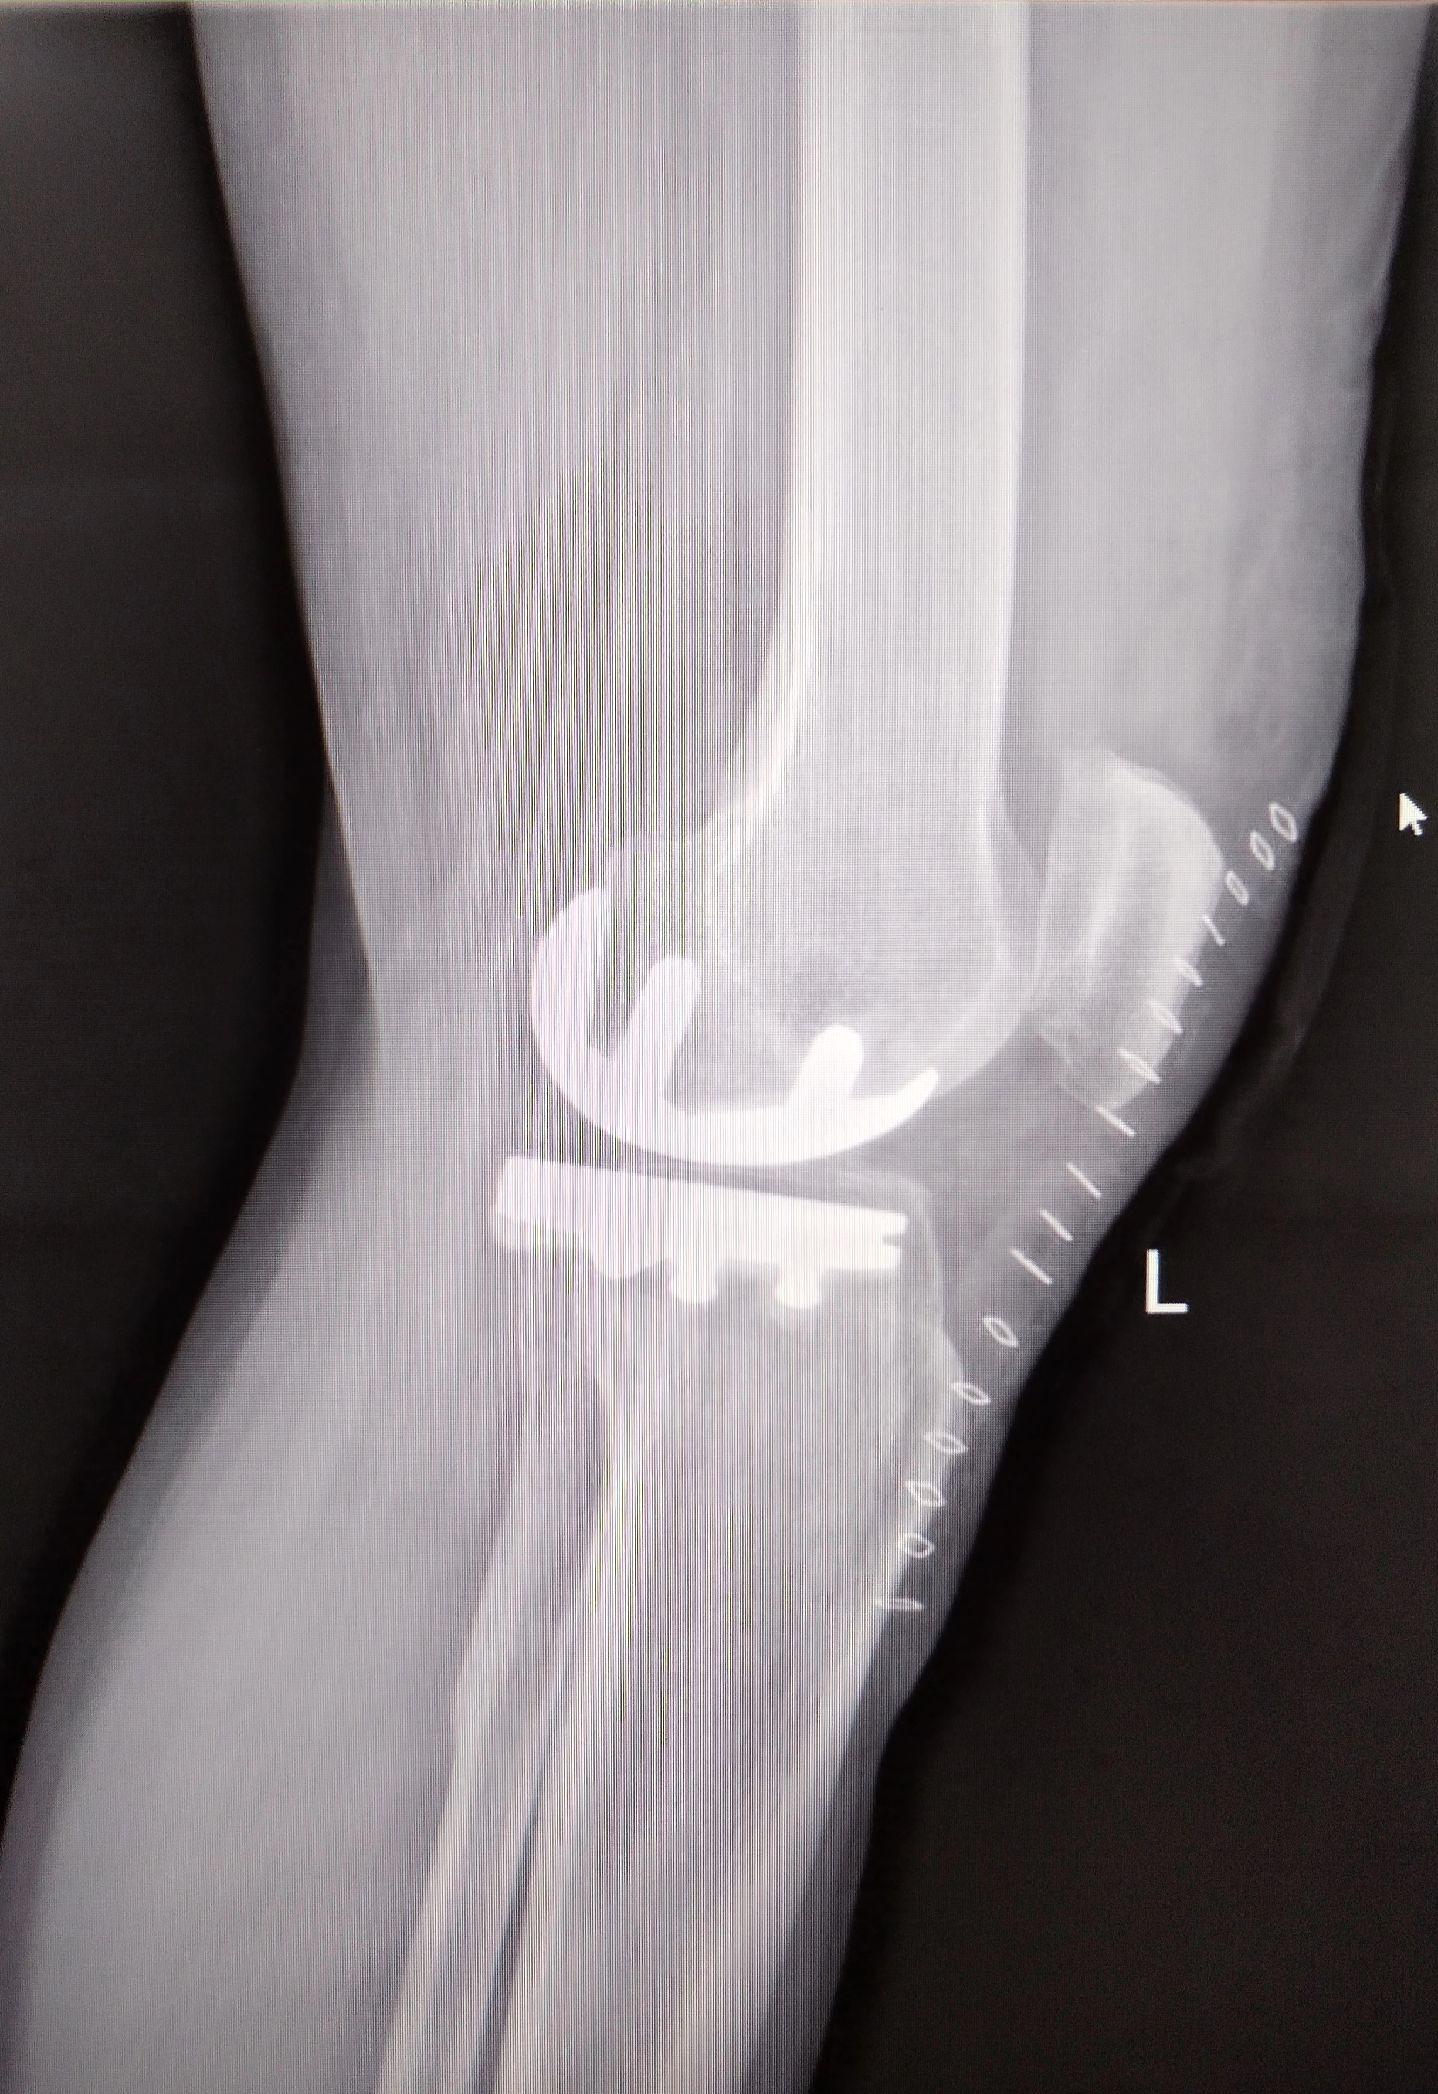

单髁置换术。(看图猜假体)每款假体都有自己的优点,不要单纯追求国产或进口,也不要单纯追求活动平台或固定平台,适合自己才是最好的。愿每一位病人都能快速顺利康复🌹